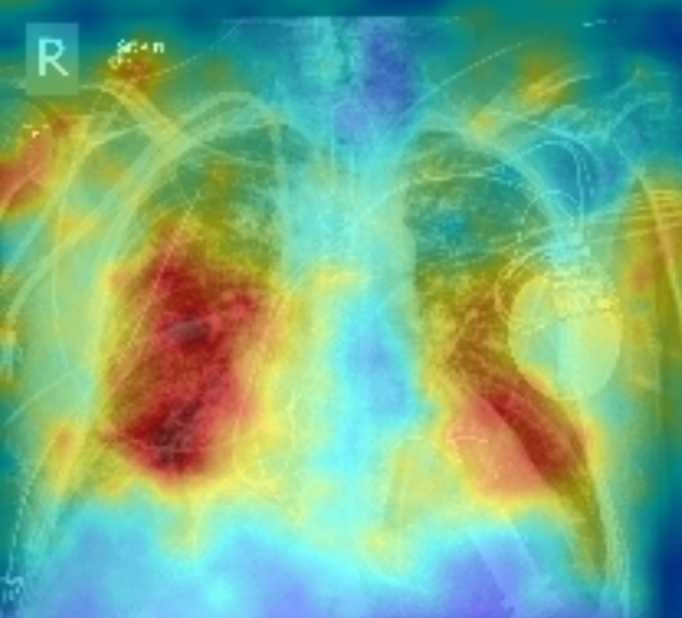

To delve deeper into the learned visual knowledge from IMITATE, we utilized Grad-CAM [57] to produce saliency maps for CXR images derived from the model in its pre-trained state. We select two CXR images showcasing two prevalent diseases, Edema and Lung Opacity. Notably, each of these images comes with ground truth annotation pinpointing the region of concern, as documented in [58]. As evident from Fig. 5, IMITATE boasts an impressive capability to accurately delineate the clinical regions of concern in the CXR images, outperforming its counterpart MGCA [4]. This is particularly noteworthy considering that IMITATE achieves this precision without relying on any external prompts or the need for additional model fine-tuning.